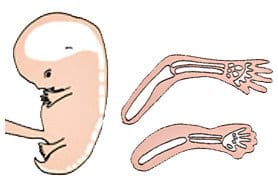

Il feto prosegue la sua ossificazione durante tutto il terzo mese di gestazione. Le ossa iniziano a formarsi a partire dai centri di ossificazione e le cartilagini sono sostituite da delle ossa. Nel frattempo, l’ossificazione della colonna vertebrale continua. ...